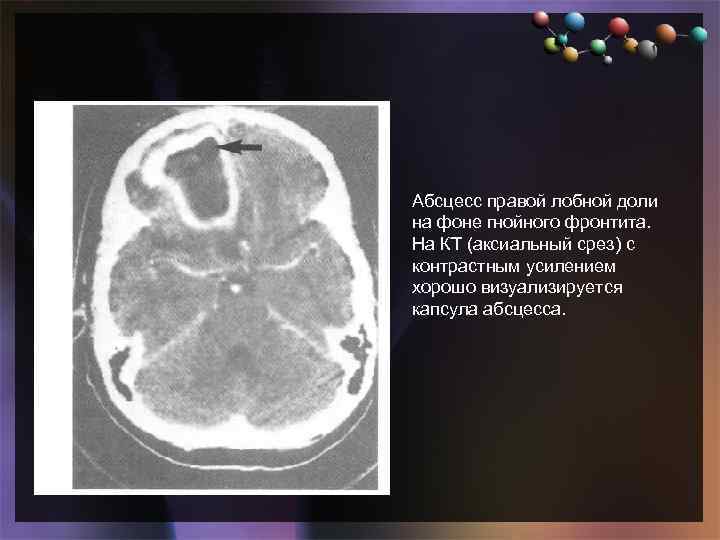

• Подзаголовок слайда Абсцесс правой лобной доли на фоне гнойного фронтита. На КТ (аксиальный срез) с контрастным усилением хорошо визуализируется капсула абсцесса.

• Подзаголовок слайда Абсцесс правой лобной доли на фоне гнойного фронтита. На КТ (аксиальный срез) с контрастным усилением хорошо визуализируется капсула абсцесса.